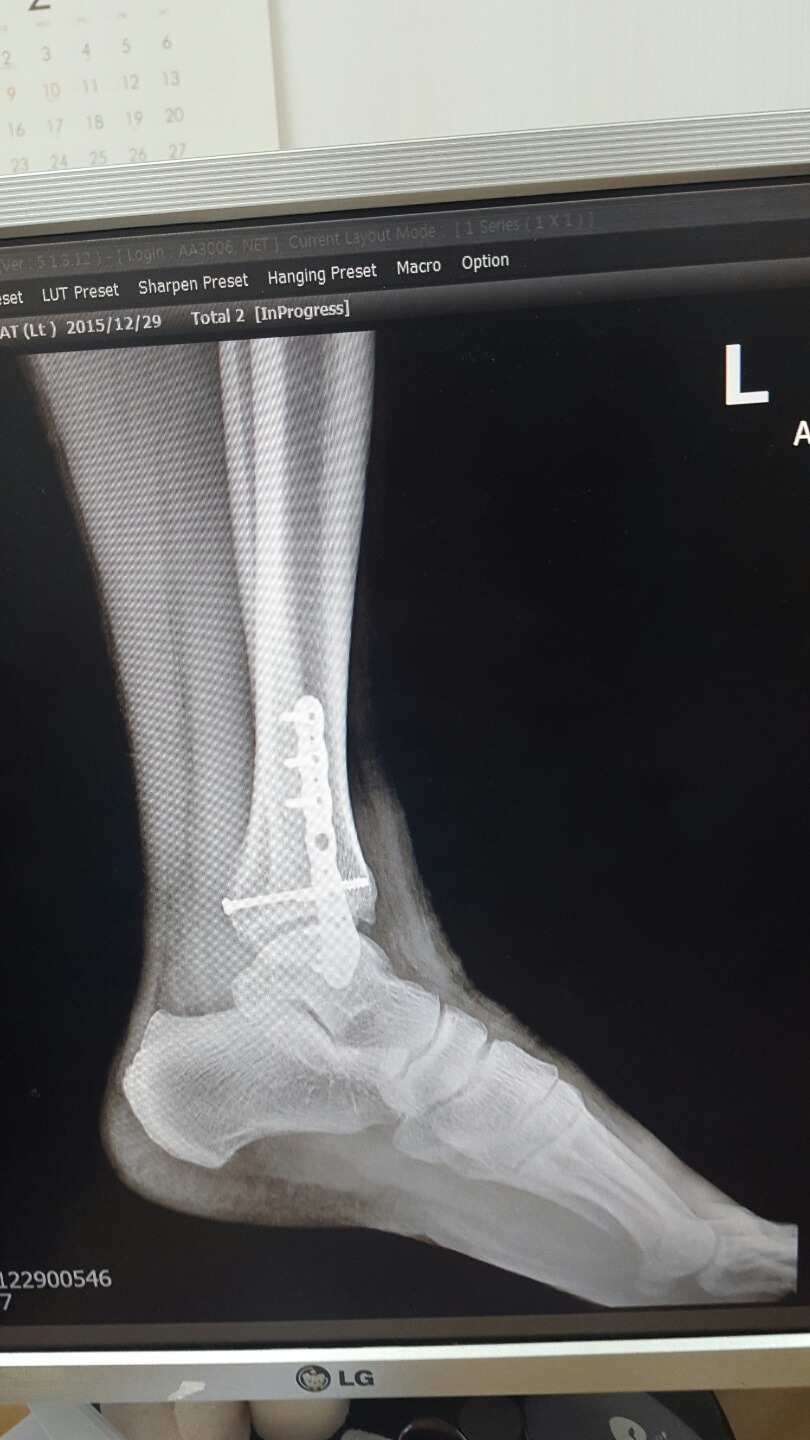

2015년 12월 29일(화)

역시 사진 먼저찍고 기다리다 순번에따라 진료실에 들어갔더니

골진이 많이 나와서 뼈가 잘 붙어가고있다는 희망적인 말을 듣게 되었고

이제부터 체중을 싣고 걸음연습을 하라고했다. 날아갈 듯 기뻤다.

회복속도가 엄청 빠르다는 이야기.